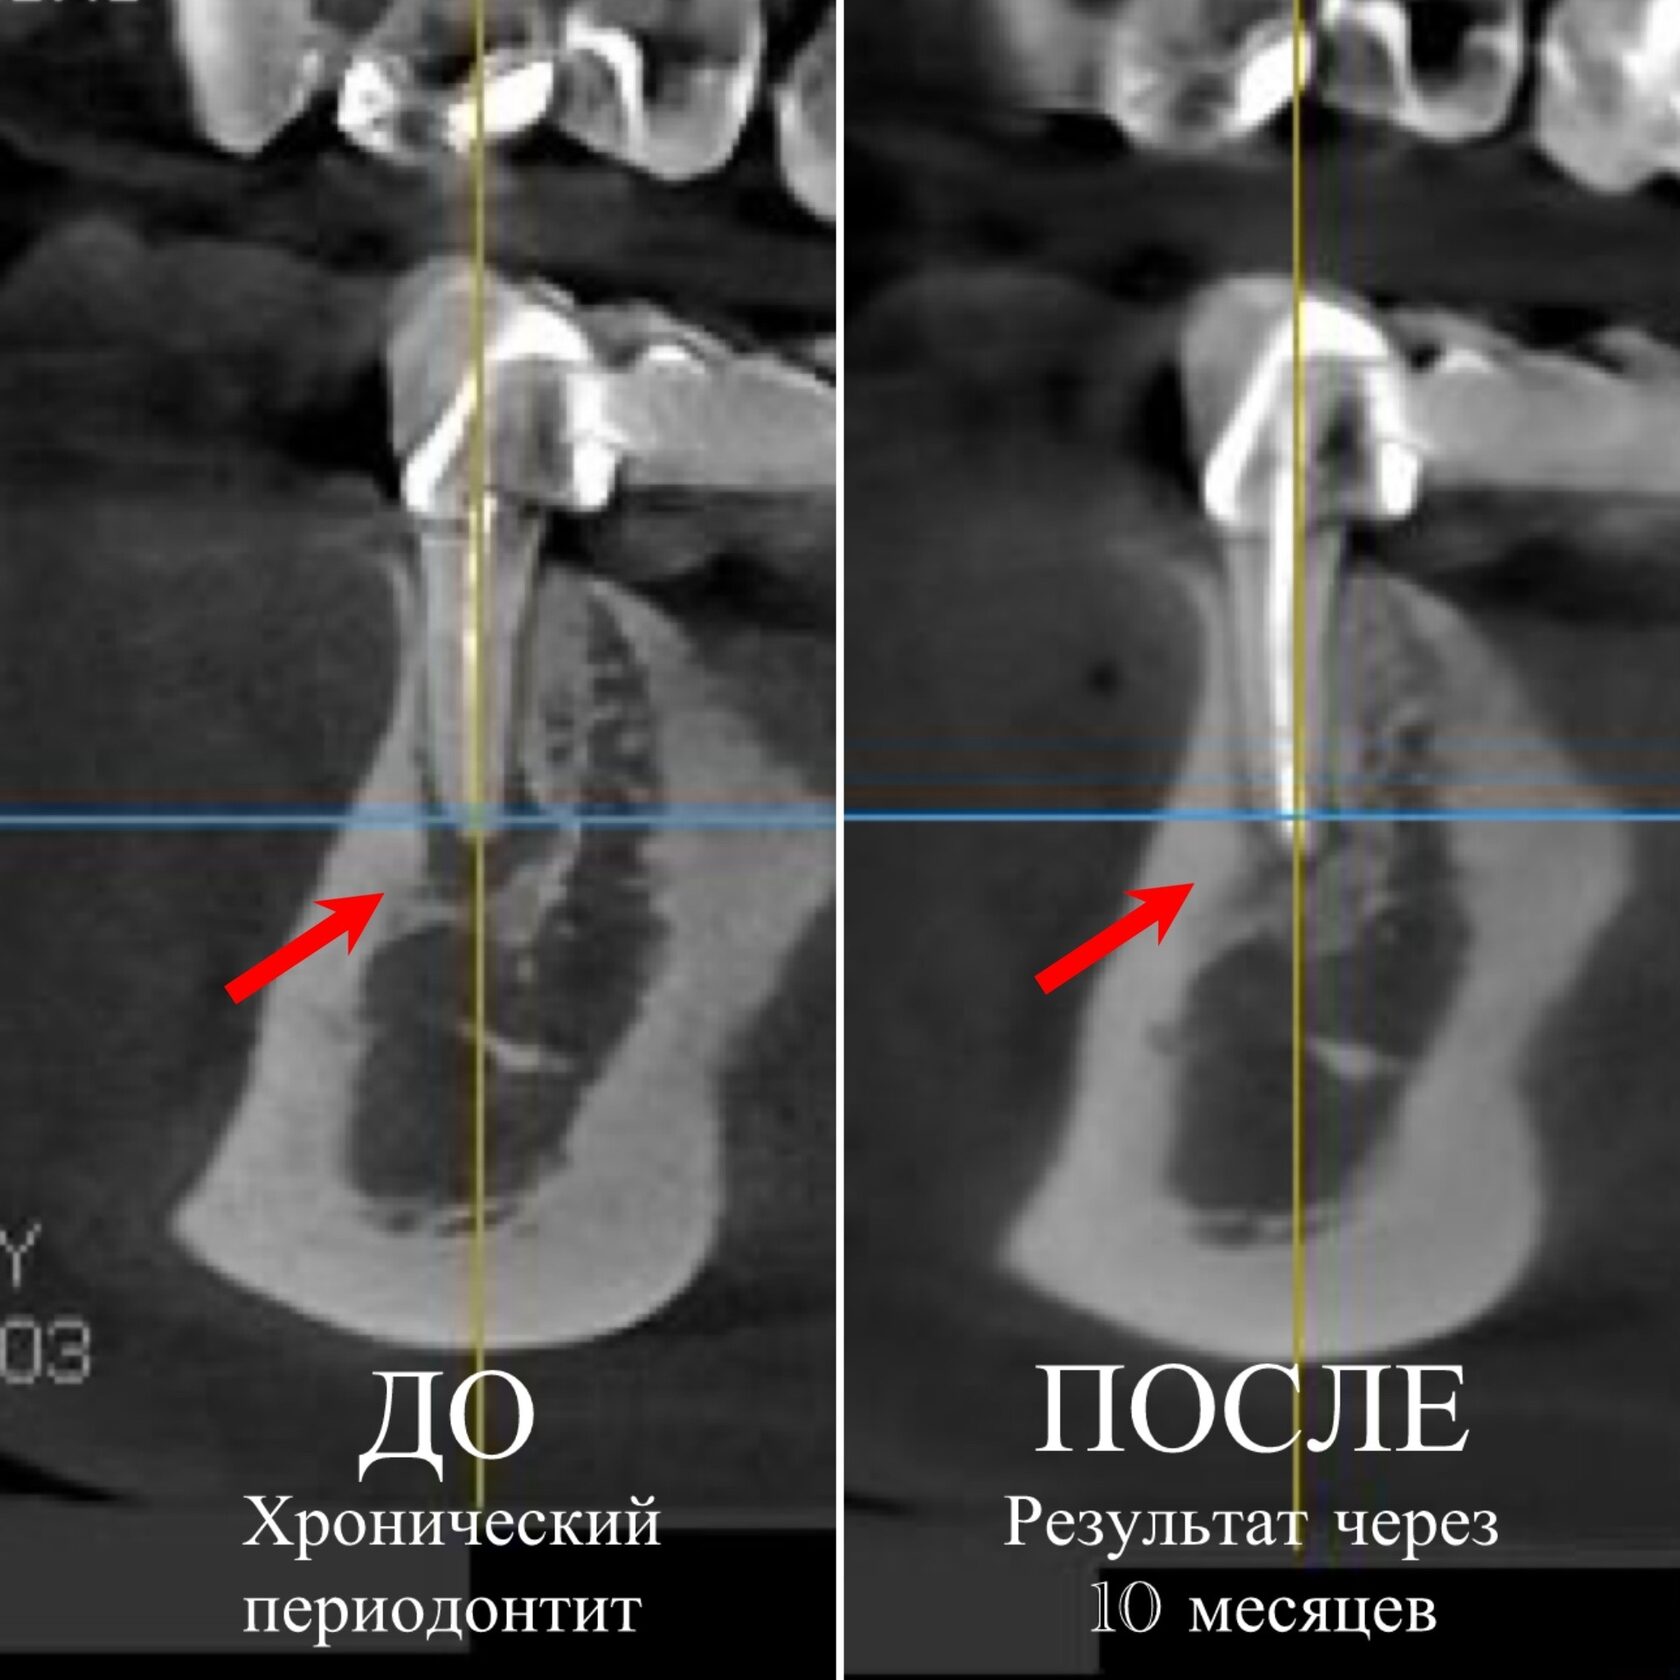

Сделали снимок и обнаружили кисту или хронический апикальный периодонтит.

В данном случае лечение проводилось через коронку в 2 этапа и заняло 2 недели, сначала мы провели медикаментозную и механическую обработку, внесли в корневой канал лекарство и после чего мы выполнили повторную обработку и пломбировку, а через 10 месяцев провели контрольный осмотр.

Окончательный результат на втором снимке. Четко видно, что кость восстановилась. Отличный результат!